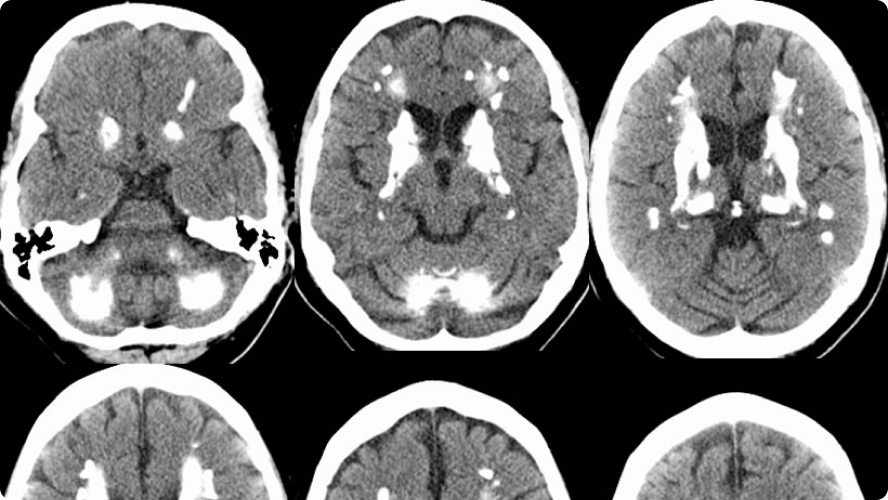

Fahr’s disease, also known as bilateral striatopallidodentatecalcinosis, is characterized by abnormal vascular calcium deposition, particularly in the basal ganglia, cerebellar dentate nucleiand white matterwith subsequent atrophy.